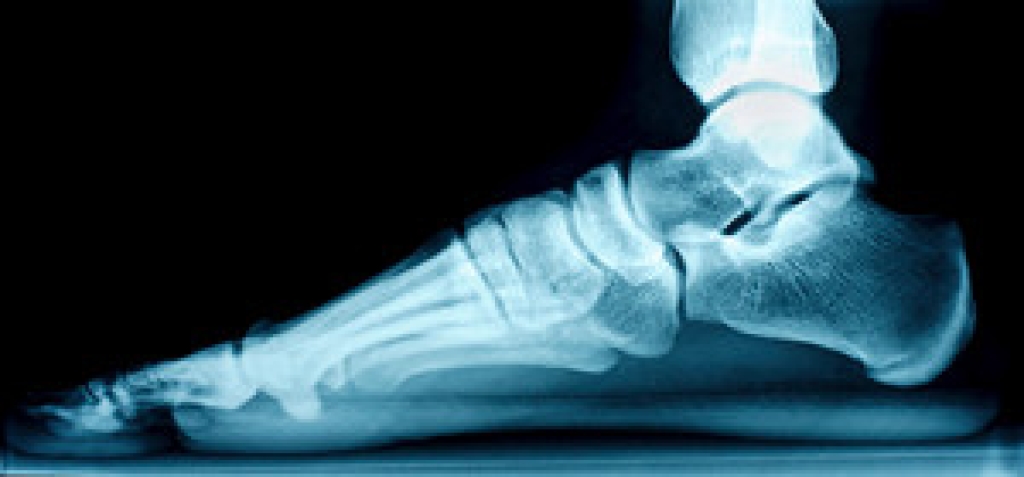

Many runners know the importance of preventing running injuries. This is helpful in avoiding injuries that are caused by over training, wearing improper shoes, or running excess miles in limited time. Research has indicated it is beneficial to have your feet properly measured to determine correct size shoe. Additionally, shoes can lose cushioning as they are worn, and it is helpful to replace running shoes approximately every 500 miles. Performing routine stretches can loosen the muscles, tendons, and ligaments of the foot, and this is important in possibly preventing running injuries. If you are considering spending time running or jogging, please consult with a podiatrist who can guide you toward techniques that can prevent running injuries.

- Have a Formal Gait Analysis – Poor biomechanics can easily cause injury